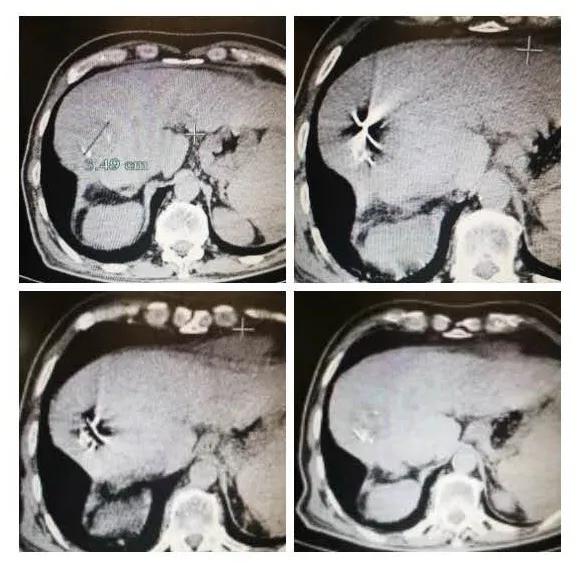

上个月我治疗的李阿公,10多年前就查出有慢性乙型病毒性肝炎,现在因为右上腹痛来院就诊,被确诊为肝癌。当时我给他做了介入治疗。这两天来复查,肿瘤缩小了一半,肿瘤指标甲胎蛋白(AFP)从术前2.4万多降到目前的2000多,效果非常显著。

有的时候,肝癌可以控制很好,不需要进一步治疗,但有时,仍然会有部分癌组织存活,就像前面提到的李阿公,他这次复查发现仍有少部分肿瘤没有被饿死,我们再次给他做了介入治疗,发现这部分的肿瘤血管又再通了,于是把这根血管再次堵塞,类似 “打补丁” 一样,使其疗效更好。